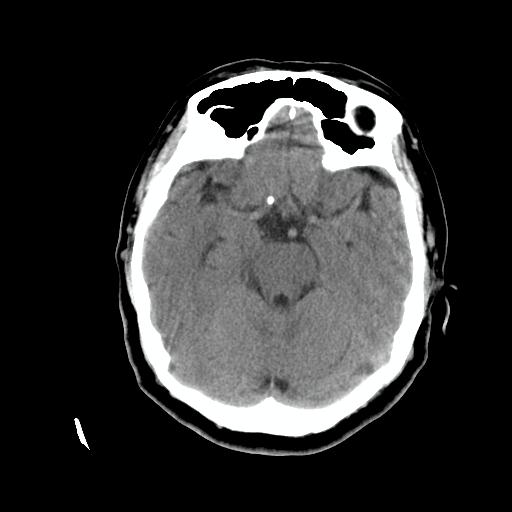

标题: CT24768:双侧脑室内囊性病变,主各位站友会诊。 [打印本页]

标题: CT24768:双侧脑室内囊性病变,主各位站友会诊。

患者女,62岁,临床提供头痛、头晕数月,无恶心及呕吐,近日加重。请各位站友看看,能否定为双侧脑室脉络丛囊肿,如果不能,应考虑什么?谢谢!

支持脉络丛囊肿,建议mr检查

支持脉络丛囊肿,建议mr检查.

支持 双侧侧脑室脉络丛囊肿;建议行mr检查。